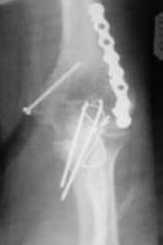

Подскажите пожалуйста, как можно в дальнейшем этому больному помочь. В марте первая операция, пришлось оперировать на 16 сутки в виду инфицированных садин и анемии. Заживление первичным натяжением,раняя разработка после операции, а через 2 нед болевой синдром,и постепенно движения в локтевом суставе ограничились до полного анкилоза. Повторно через 4 месяца вторая операция" артролиз,удаление оссификатов, удаление фиксаторов, реостеосинтез этой же реконструкционной пластиной и винтом" интраоперационно после удаления оссификатов и фиксаторов обнаружил, что перелом не сросшиеся, поэтому пришлось синтезировать заново. Зажило рана первично, объем движений в локтевом суставе сгибание 70, разгибание160, ротационные движения востановились полностью,вроде бы успокоились. Опять постепенно в течении 8 нед после повторной операции постепенно движения ограничились до 80 - 110, на снимке оссификат. Снимки во вложении, буду рад Вашим советам. Спасибо!